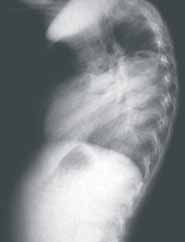

El único hallazgo al examen físico fue disminución de los ruidos respiratorios en el hemitórax izquierdo. No se le encontró ninguna otra malformación asociada. Los rayos X mostraron desplazamiento de la silueta cardiomediastínica hacia la derecha, con opacidad en base pulmonar izquierda y posterobasal en la proyección lateral (ver Figuras 1 y 2). (Ver: Factores asociados a complicaciones debidas a la realización de broncoscopias en pacientes pediátricos)

Figura 2. Radiografía de tórax. Proyección lateral